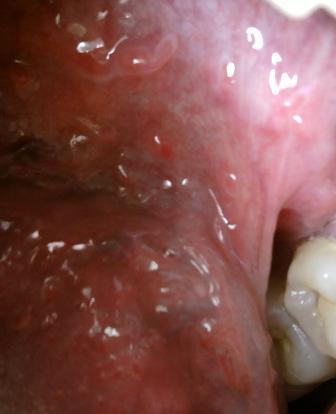

石家庄九州皮肤病医院 > 尖锐湿疣 > > > 尖锐湿疣是性病吗?尖锐湿疣属于性病中的一种,患病之后大家应该去医院接受正规的治疗,因为任何疾病只有在早期接受专业的治疗才可以达到很好的治愈疾病的目的,关于尖锐湿疣的治疗不可以盲目,对因对症治疗是很关键的。

尖锐湿疣是性病吗?尖锐湿疣在性病中的发病率是 比较高的,并且在治疗上有一定的难度,因此建议大家在患病之后及时接受正规的治疗,坚持 治疗,听从医师的安排是很关键的。尖锐湿疣发病和不洁净的性行为有很大的关系,所以为了自身健康,建议大家应该早发现早治疗。任何疾病早期都是治疗疾病的关键时期。尖锐湿疣患者应该远离辛辣刺激性的食物,比如:辣椒,葱姜蒜等扥海鲜和烟酒也是要远离的,以免刺激而加重疾病的发展。

尖锐湿疣是性病吗?尖锐湿疣危害巨大,长时间持续性感染高危险型的尖锐湿疣,有可能会造成癌前病变以及侵袭性癌,以上就是石家庄九州医院专家的解答,希望可以帮助到您。如有任何不清楚的可以拨打石家庄治疗尖锐湿疣的医院九州皮肤病医院康复热线:0311-89109686和专家取得联系。我们的专家小组在医院诊治方面积累了丰富的临床经验,通过康复病人之间的口口相传,患者前来接受治疗的是最佳选择。